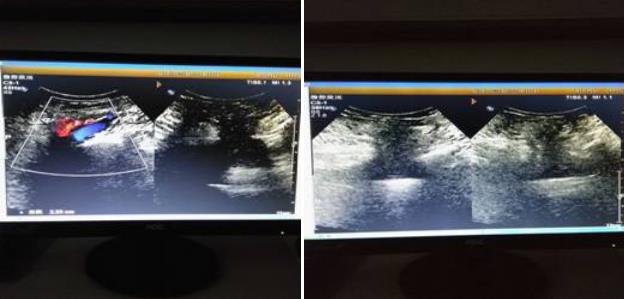

超聲所見(jiàn):右下腹患者自述“腫物”處探查:距體表約0.8㎝處,探及長(zhǎng)度約14.8㎝不均質(zhì)偏強(qiáng)回聲,中心部較大厚度5.4㎝,邊界清晰,于該腫物后方探及寬度約2.8㎝似為回聲失落處,于該處偏內(nèi)側(cè)探及股動(dòng)靜脈。右側(cè)腹股溝區(qū)探及扁橢圓形淋巴結(jié),較大者0.77*0.56/0.8*0.5㎝。

診斷意見(jiàn):右下腹部近腹股溝區(qū)偏強(qiáng)回聲腫物--考慮為股疝,內(nèi)為網(wǎng)膜可能,因腫物巨大探查受限,不除外其他,請(qǐng)結(jié)合其他檢查。

后經(jīng)臨床手術(shù)證實(shí),為右側(cè)巨大股疝,內(nèi)容物為大網(wǎng)膜。

超聲表現(xiàn):疝囊位置是超聲診斷股疝的重要依據(jù)。根據(jù)股疝疝囊大小及內(nèi)容物的不同,其超聲表現(xiàn)略有差別。典型股疝的疝囊一般較小,常位于腹股溝韌帶下方的股內(nèi)側(cè),其外側(cè)為股靜脈;若疝囊較大時(shí),可移位至腹股溝韌帶上方或恥骨聯(lián)合處。仔細(xì)檢查可見(jiàn)疝囊于腹股溝韌帶后方經(jīng)較窄的頸部與腹腔相通;咳嗽或乏氏運(yùn)動(dòng)時(shí),疝囊大小可略有增大或無(wú)顯著變化。疝囊內(nèi)容物可為網(wǎng)膜組織,呈中強(qiáng)回聲;也可為腸管,聲像圖顯示為管腔樣結(jié)構(gòu);若病程較長(zhǎng)時(shí),疝囊內(nèi)可見(jiàn)無(wú)回聲積液。股疝嵌頓時(shí),疝囊內(nèi)腸管腫脹壓痛,可同時(shí)伴有腹腔內(nèi)腸管擴(kuò)張。鑒別診斷